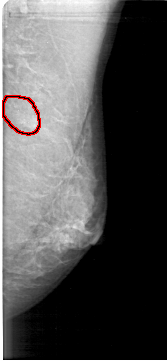

D_4165_1.RIGHT_MLO

LEFT_CC LINES 4801 PIXELS_PER_LINE 1966 BITS_PER_PIXEL 12 RESOLUTION 43.5 OVERLAY

FILE: D_4165_1.LEFT_CC.OVERLAY

TOTAL_ABNORMALITIES 1

ABNORMALITY 1

LESION_TYPE CALCIFICATION TYPE ROUND_AND_REGULAR-PLEOMORPHIC DISTRIBUTION CLUSTERED

ASSESSMENT 0

SUBTLETY 3

PATHOLOGY BENIGN

TOTAL_OUTLINES 1

BOUNDARY